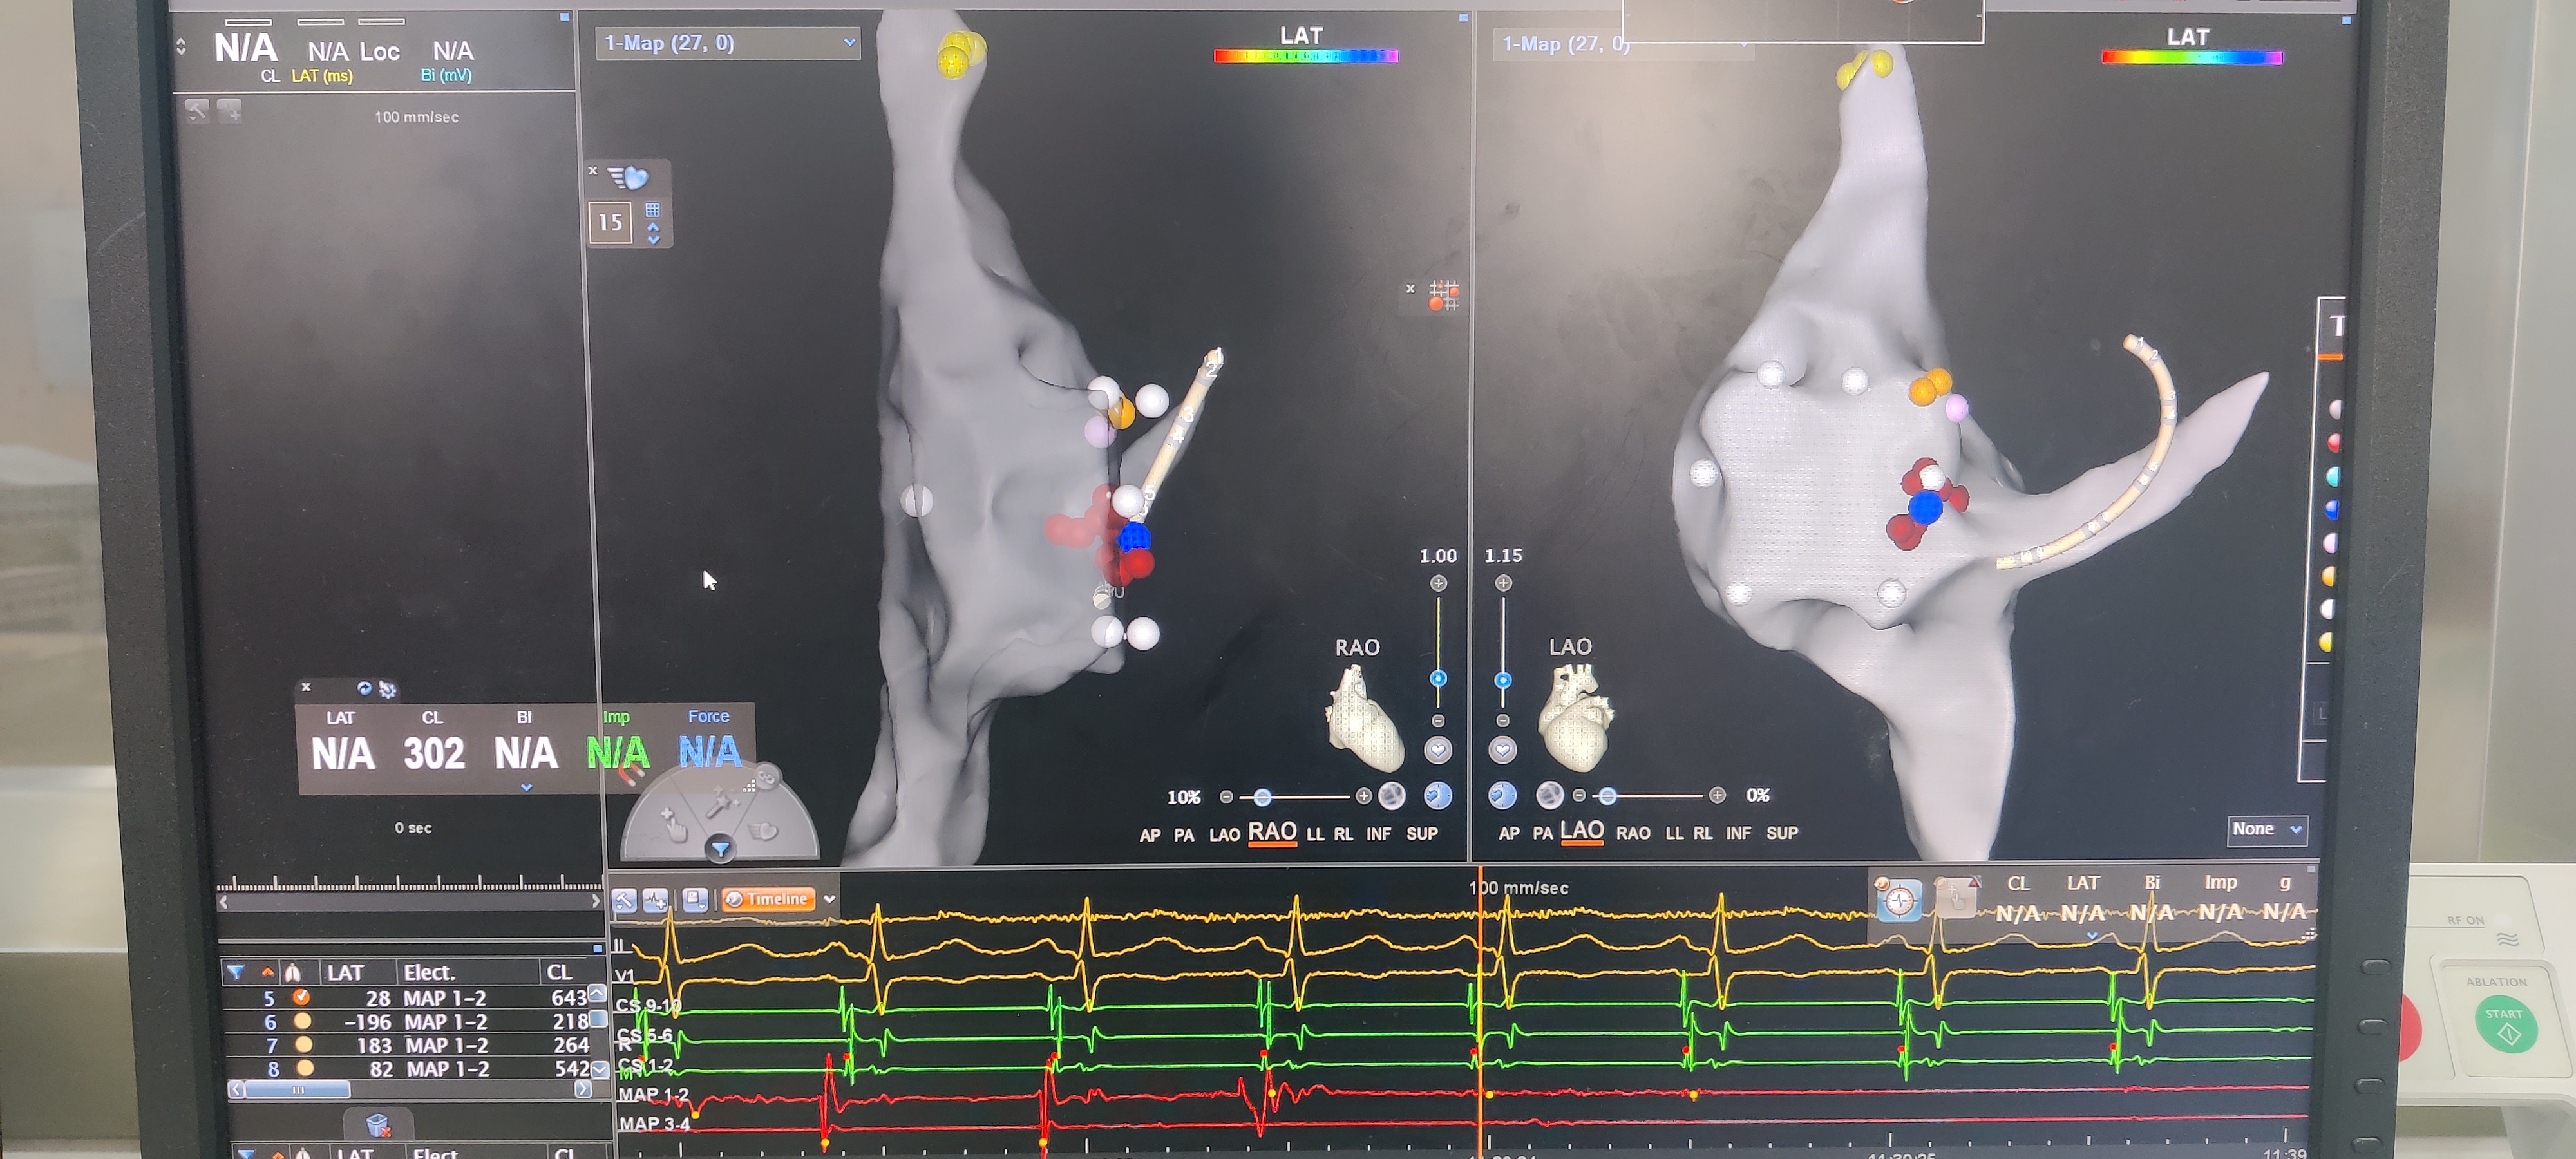

经过术前充分准备,在科室晋军主任的带领下,谭虎副主任率电生理团队通力合作,在产科老师的围术期支持下,在三维标测系统辅助下,全程零射线,找到病灶靶点之后,心动过速被成功终止,因为是二次射频消融术,术中也反复观察及验证,确保消融疗效。

“传统的射频消融,医生需要在射线下指导手术,射线可能对孕妇,尤其是对胎儿的发育造成影响。”谭虎教授表示,现在采用的是磁场、电场双重定位系统的三维标测系统辅导方法,全程零射线,在三维指导下来进行射频消融,通过这个三维标测系统辅导方法,能够精准找到引起心律失常机制的点,精准的把这个病灶去除,既没有副作用,又达到了一个非常完美的效果。”